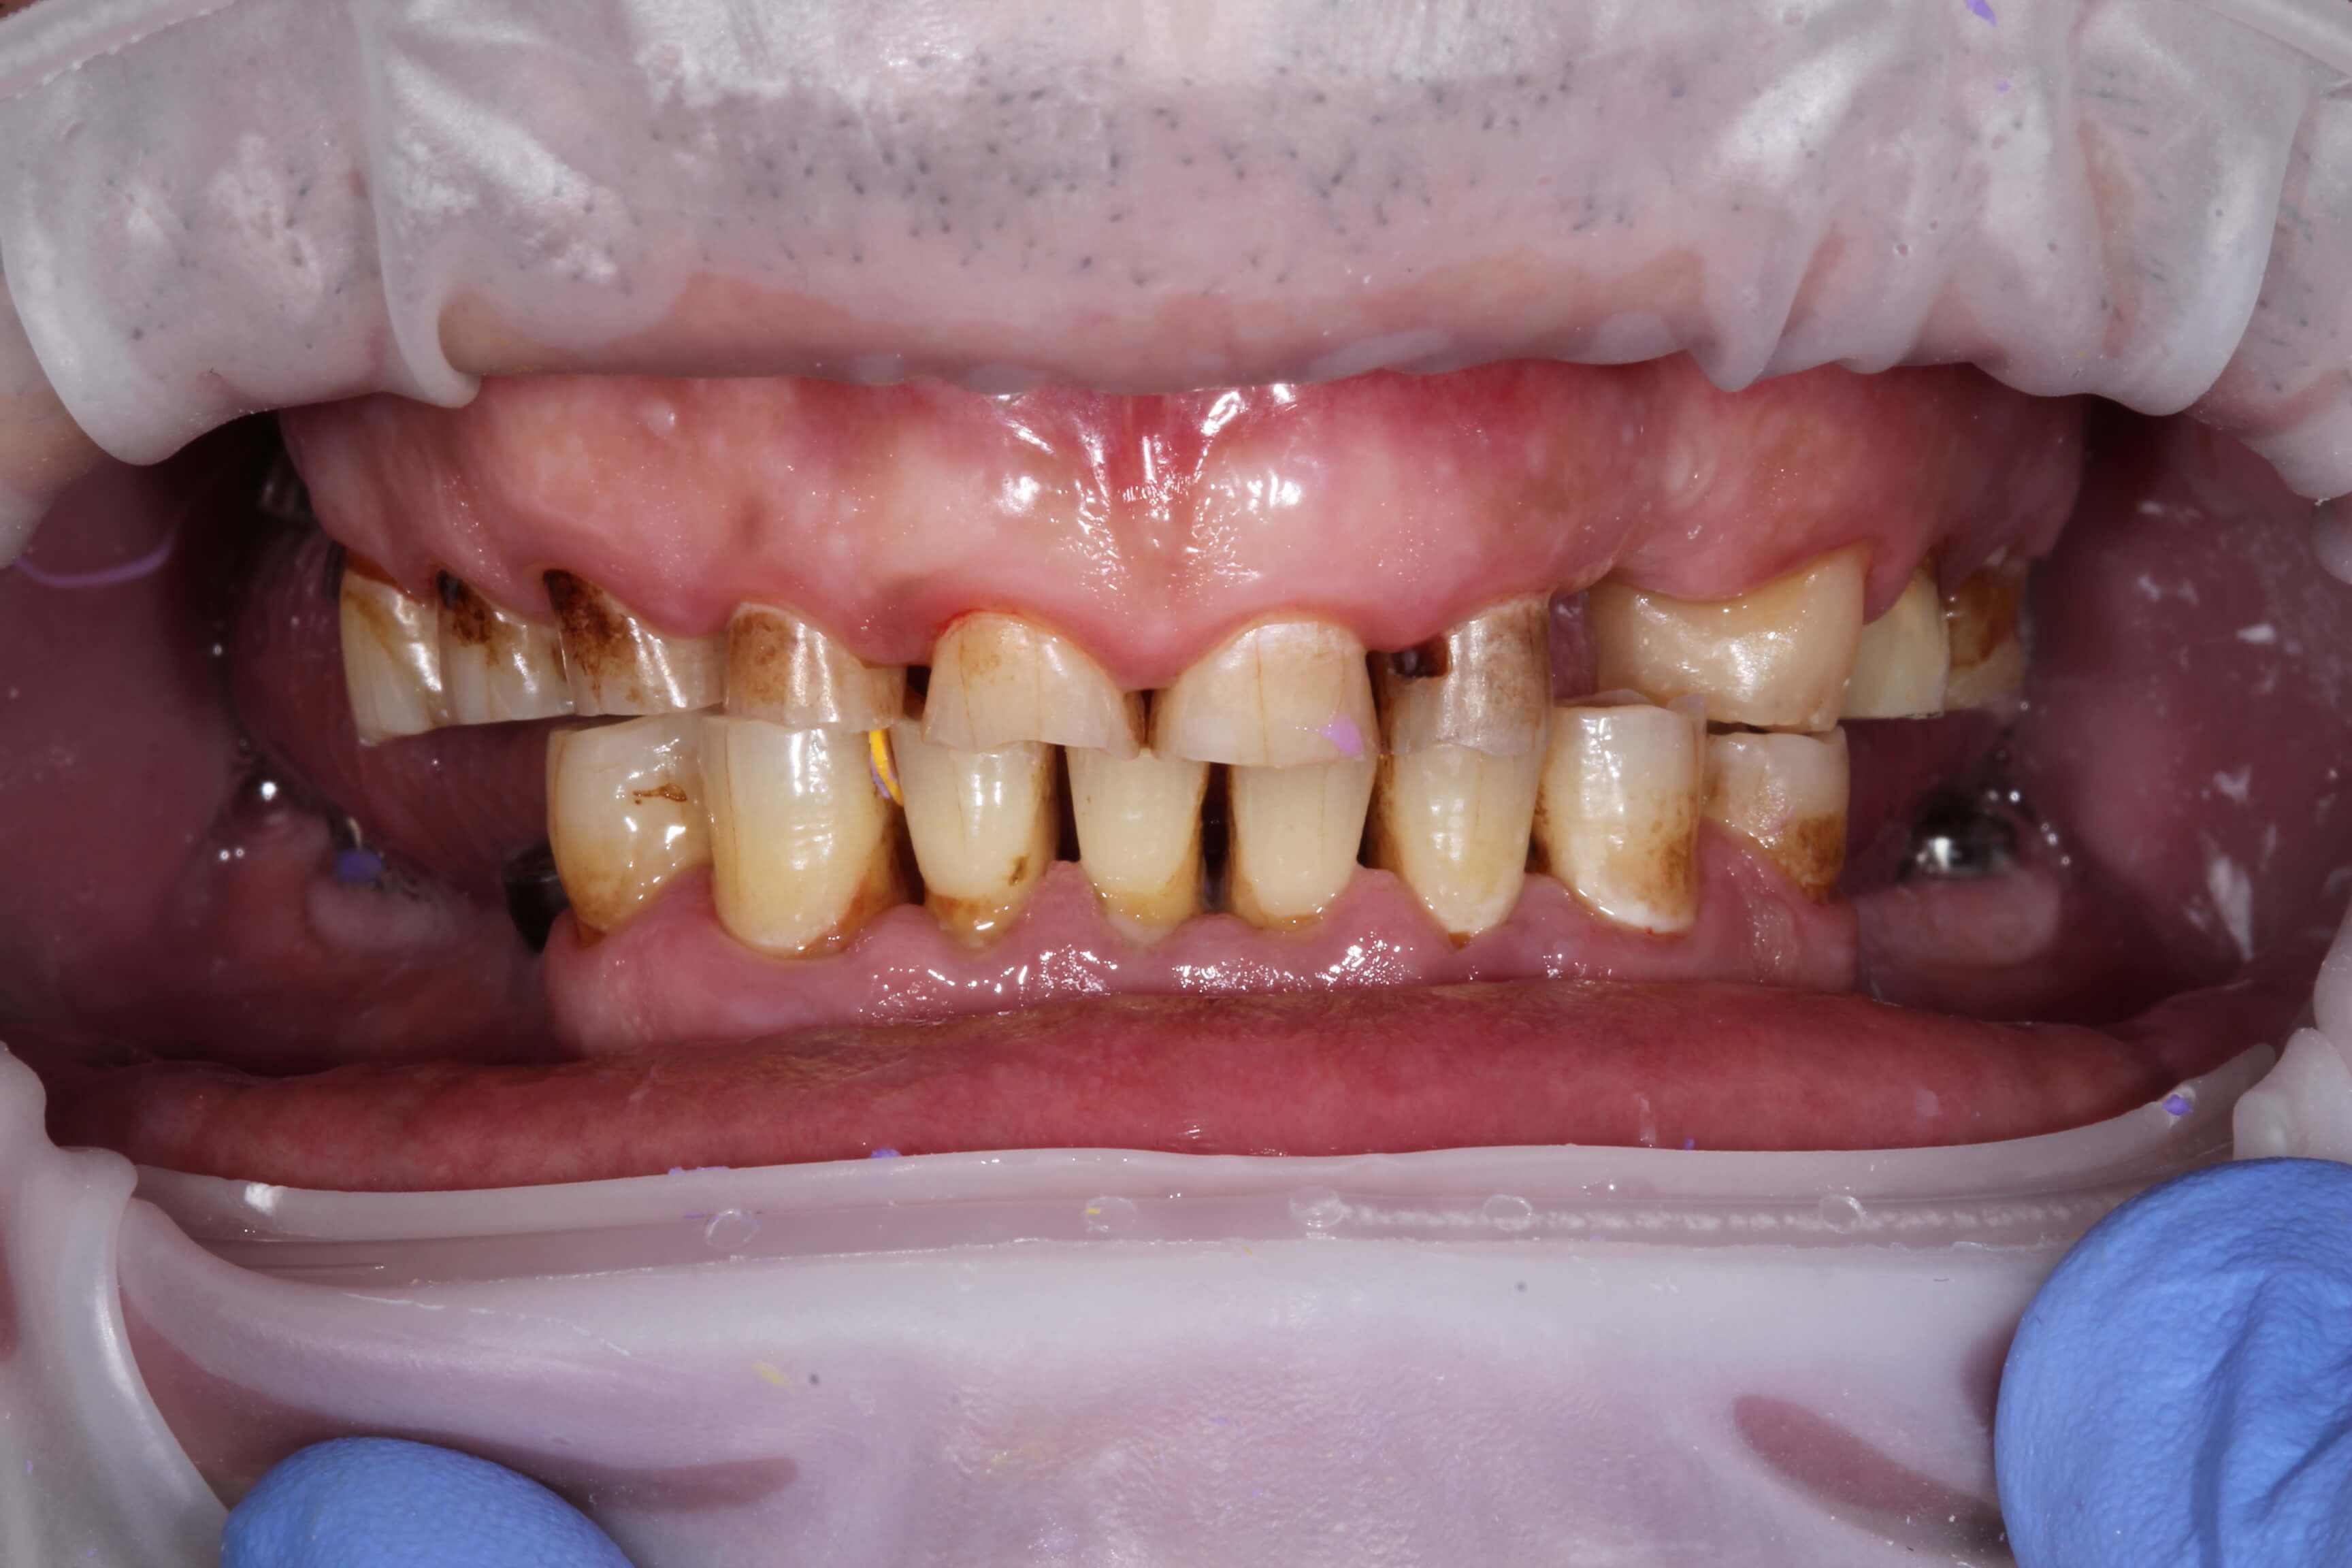

A male patient came to us with complaints of severe wear of the front teeth and the absence of posterior teeth in both jaws. He initially sent us X-rays and photos of his teeth remotely, which allowed us to create a detailed, personalized treatment plan that we later carried out.

At the first visit, the remaining tooth roots were removed, and implants were placed in the posterior areas where teeth were missing. After that, soft tissue grafting was performed in the necessary sites.

After six months, following digital modeling of the future restoration, the posterior teeth were restored with zirconia crowns on implants, while the anterior teeth were restored with ceramic veneers and crowns.